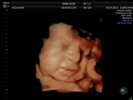

Fotografías de ecografías 4D HD/5D

Haga click sobre las imágenes para ampliar